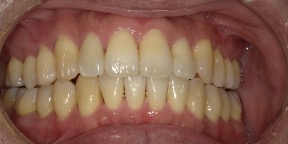

33歳女性のビフォーアフター

| 診断 | 空隙 |

| 治療方針 | 治療方針:前歯の咬合関係改善と空隙閉鎖を主な目的にて主にIPR(歯と歯の間をわずかに削合してスペースを獲得する方法)を組み込んだ動的矯正治療を行い、空隙、前歯咬合を改善後、保定を行う。臼歯部の咬合関係はプランの都合上維持することとした。 |

| 治療費 ※ | 67万8千円(診断、型取り、矯正中のメンテナンス、保定装置を含む料金) |

| 治療期間 | 6か月 |

| リスク | 1日20時間以上マウスピースを使用できない場合、歯が動かなかったり、想定しない誤差により不完全に終わる可能性がある。装着時や食事時に痛みを伴う。歯肉退縮や虫歯になるおそれがある。また、指導通りに装着できていない場合や適切なブラッシングが出来ていないとそのリスクが高くなる。歯根が短くなることがある。ごくまれに歯の神経が損傷してしまうことがある。過去にぶつけたり深い虫歯治療をしたことがあるとそのリスクはやや高くなる。矯正後には保定装置が必要。適切な使用ができない場合、後戻りの原因となる。将来的に歯並びが動いて再矯正が必要な場合がある。親知らずが正常に生えていない場合、その可能性がやや高くなる。 |